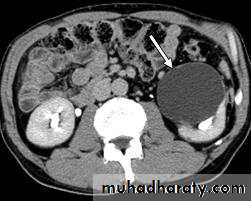

Renal S.O.L (cyst)

RENAL CYST

IVU :-* Nephrogram shows filling defect .

*Displacement , elongation & stretching of PCS which depend on size and site of the cyst .

US :-

shows echo-free cystic lesion with posterior enhancement.